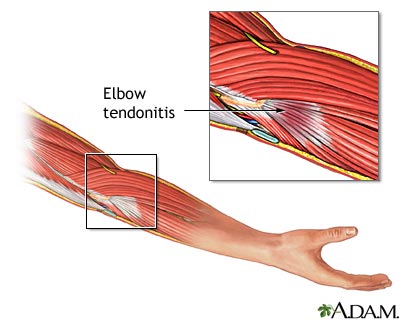

Tendons are the fibrous structures that join muscles to bones. When these tendons become swollen or inflamed, it is called tendinitis. In many cases, tendinosis (tendon degeneration) is also present.

Tendinitis can occur as a result of injury or overuse. Playing sports is a common cause. Tendinitis also can occur with aging as the tendon loses elasticity. Body-wide (systemic) diseases, such as rheumatoid arthritis or diabetes, can also lead to tendinitis.

- Elbow

The tendon can be inflamed, and the skin over it may be warm and red.